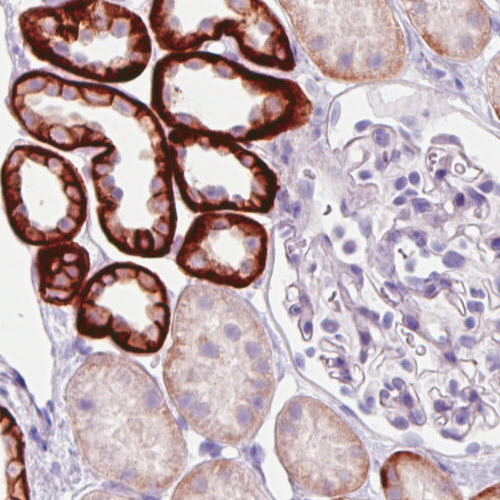

Immunohistochemical staining of human kidney shows strong membranous and/or moderate cytoplasmic immunoreactivity in subsets of renal tubules, while glomeruli are negative.